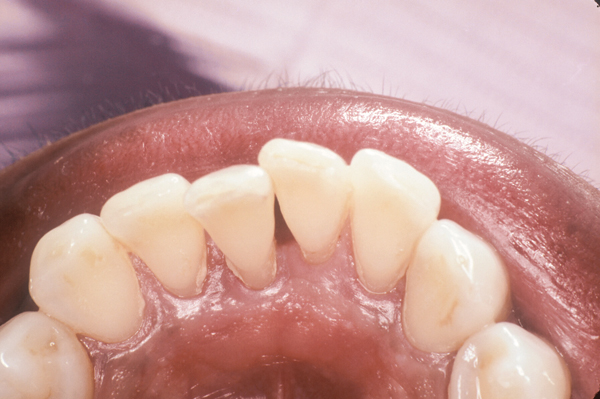

Fig 6. Class IV traumatic fracture of the incisal edges of the maxillary central incisors.

Figure 6